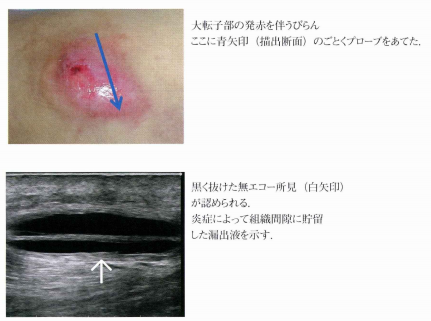

褥瘡エコーの個人的マニュアル - 南砺の病院家庭医が勉強記録を始めました。An archive of medical articlessummarized by a family physician from Nanto Municipal Hospital。

はじめての褥瘡エコー 前編 かんかん! -看護師のためのwebマガジン by 医学書院。

褥瘡エコーの個人的マニュアル - 南砺の病院家庭医が勉強記録を始めました。An archive of medical articlessummarized by a family physician from Nanto Municipal Hospital。

はじめての褥瘡エコー 前編 かんかん! -看護師のためのwebマガジン by 医学書院。

はじめての褥瘡エコー 前編 かんかん! -看護師のためのwebマガジン by 医学書院。

はじめての褥瘡エコー 前編 かんかん! -看護師のためのwebマガジン by 医学書院。